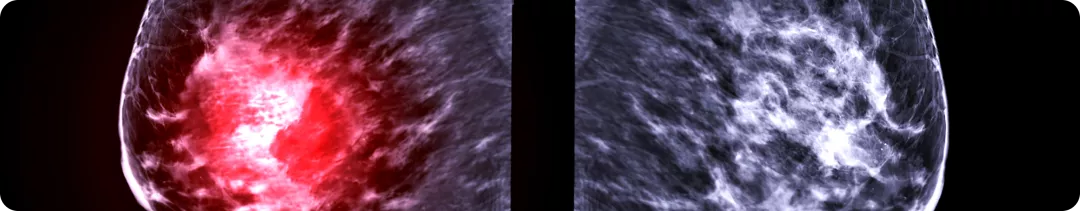

Плотность ткани молочной железы при маммографии

Повышенная маммографическая плотность ассоциирована с увеличением риска РМЖ.